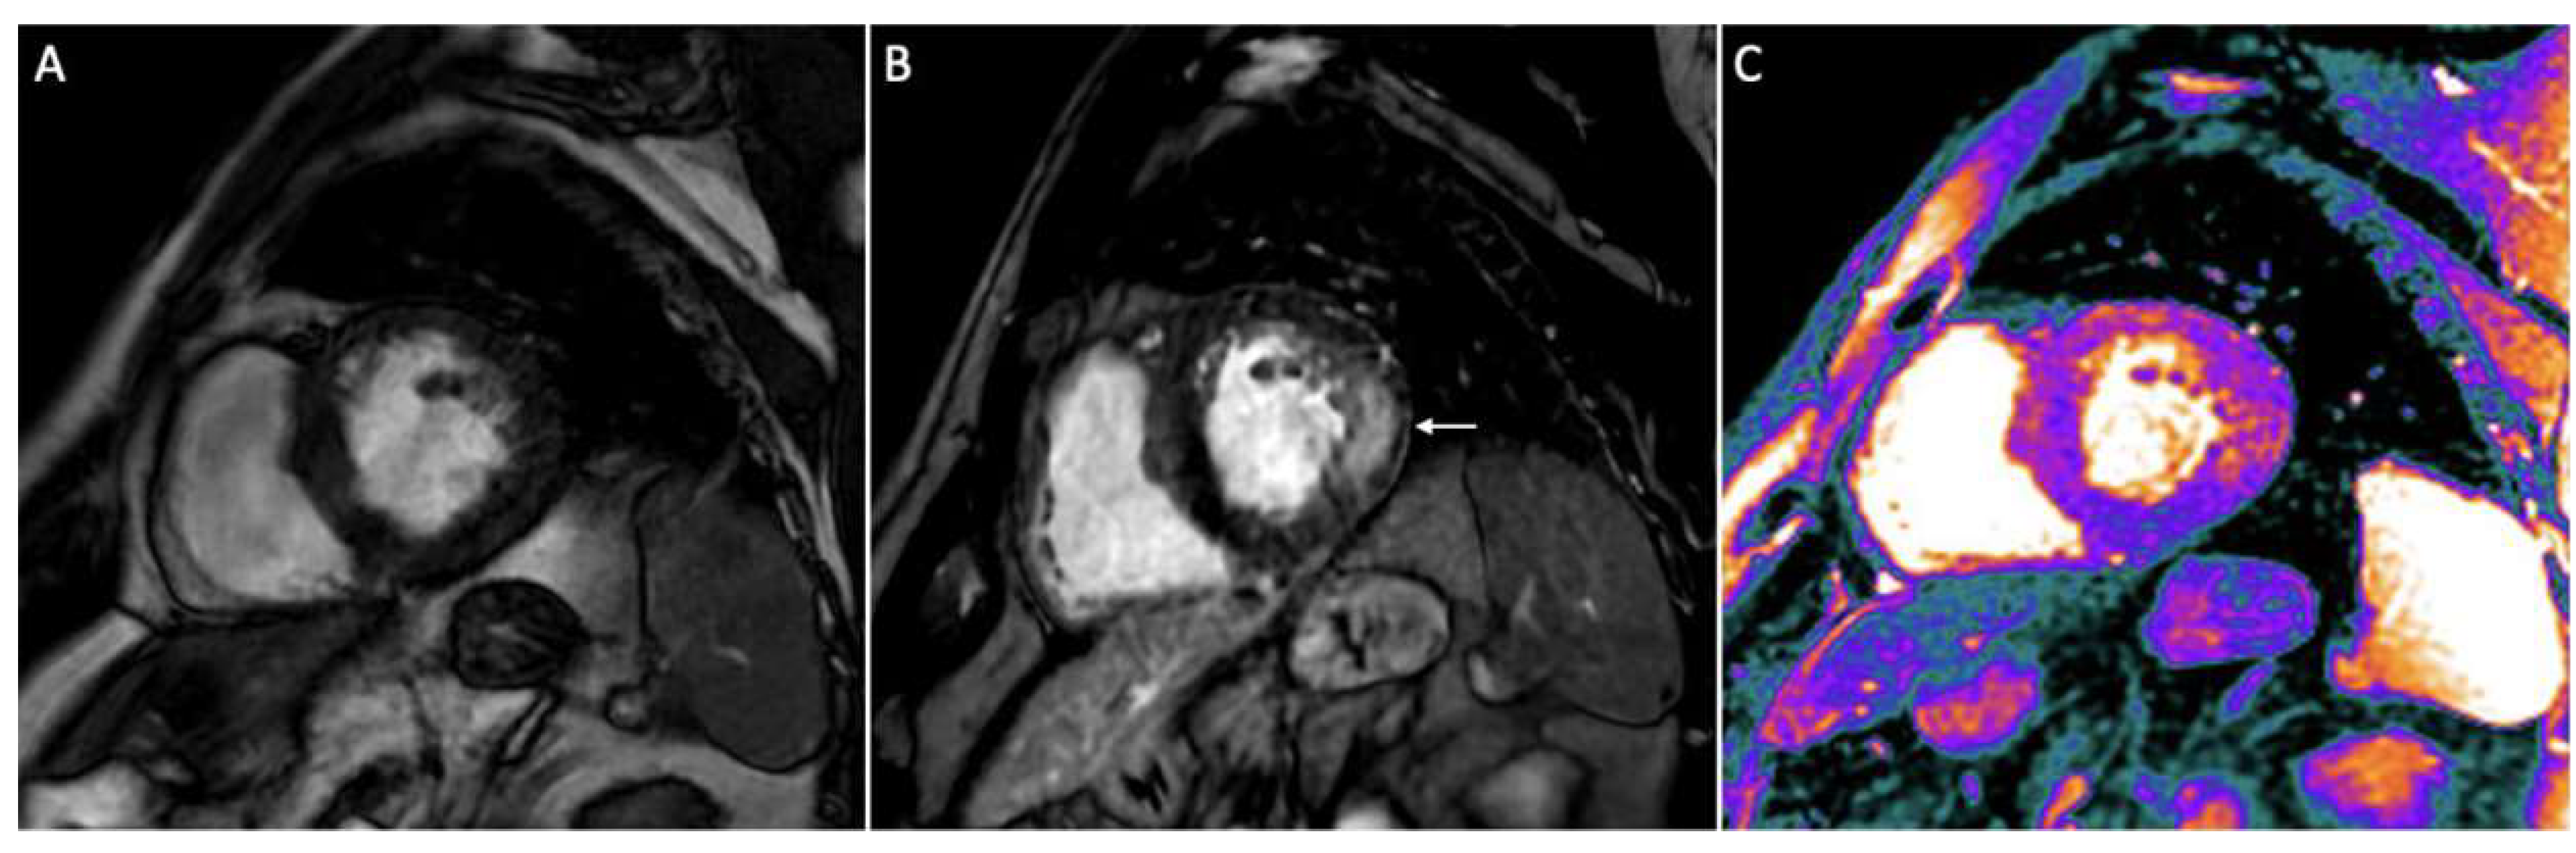

3.6. Infiltrative Cardiomyopathies

3.7. Cardiac Sarcoidosis